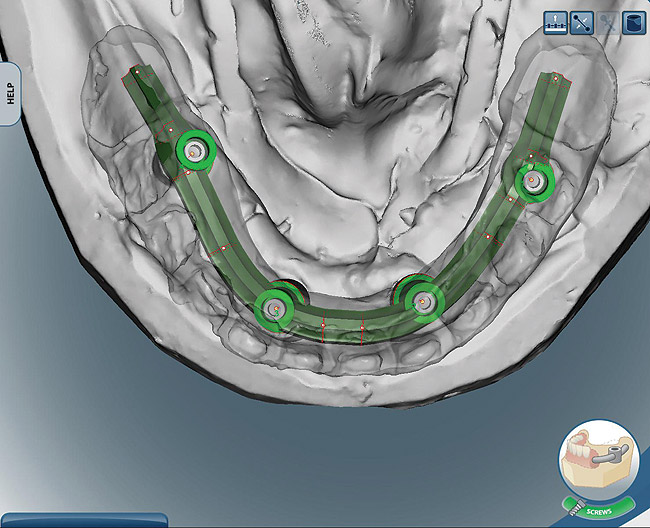

The laboratory technician made a small triad base-plate using at least two titanium provisional sleeves into the base plate. This allowed the restorative dentist to stabilize any required intermediate tooth try-ins. The teeth were set up, and a wax-up of the facial contours was produced. The facial and lingual contours of the wax-up were created as an exact replica of the finished product. The teeth were removed from the wax-up leaving a negative of the denture teeth in the wax around the arch. The master cast and baseplate without the teeth were forwarded to Nobel Biocare for scanning. Due to the fact that this particular technique and the implants can accommodate a wide range of prosthetics and abutments, high-strength zirconia or titanium substructures can be fabricated using CAD/CAM technology (Figure 8 and Figure 9).10,11 Therefore, the bar was designed on screen considering support for each tooth, and then it was milled and returned to the laboratory.

Figure 8  Upper and lower arch design of CAD/CAM titanium frames.

Figure 8

Figure 9  Upper and lower arch design of CAD/CAM titanium frames.

Figure 9